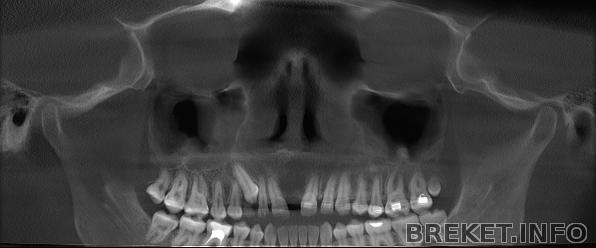

тут расширение видно во всей красе

а здесь уже можно видеть стремление зубов встретиться((( но корни не пускают их (почему-то)

AminoTabs, никуда не делся, просто в разрез не попал))) Там каждый раз дугу выстраивают по-разному в программе, чтобы этот вид получить. Вообще странно, что мне эту малышку не сказали удалить, может, потом....

там справа восьмерка-горошина. куда у нее корень делся ?